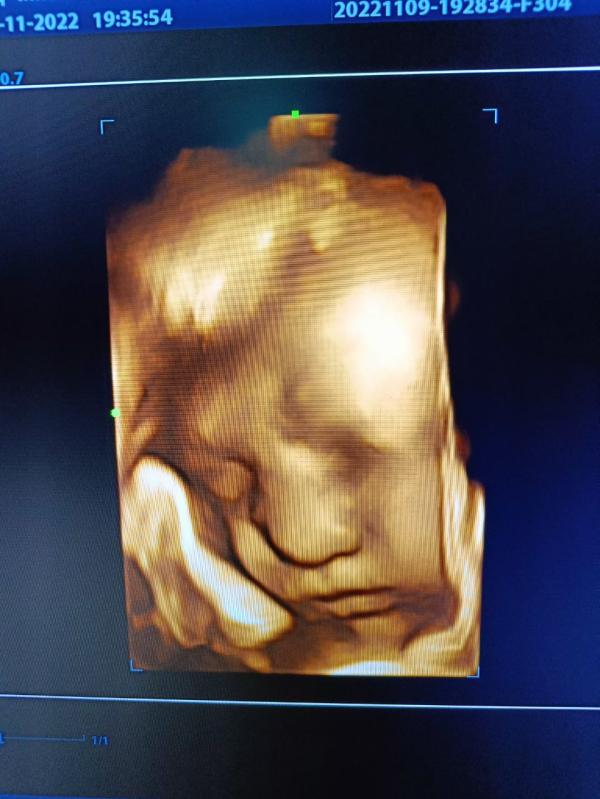

Мой мальчик 💙🤍

Совсем скоро встретимся

Впервые показал личико сегодня, на 38.4 неделе 😋

09.11.2022

крутое УЗИ, скажите это обычное УЗИ или 3д? вы сами снимали?

Это обычное УЗИ ,но нам на экране показали в 3д) на телефон муж снял